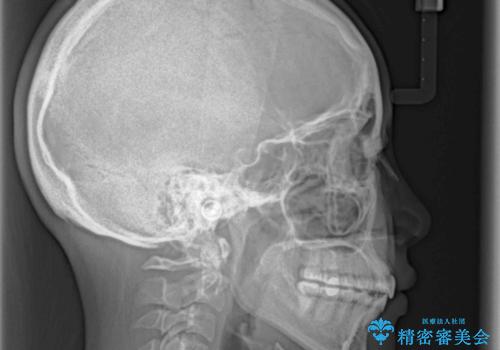

毎日しっかりと装着してくださったので、概ねシミュレーション通りに歯を移動させることができました。

治療前には接触することのなかった上下の前歯が接触するようになり、食事の際前歯でものをかみ切れるようになりました。

気にしていた口元の印象が改善され、患者様には大変満足していただきました。